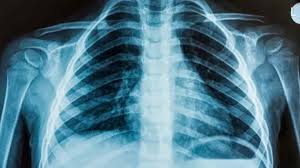

O distrito de Mossuril, em Nampula, não está a efectuar exames de Raios X devido a uma avaria do equipamento, há dez anos.

A situação tem forçado a mobilidade dos pacientes para os distritos vizinhos de Monapo, Ilha de Moçambique e Nacala-Porto, à procura deste serviço.